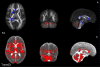

The goal of this study is to characterize the potential effect of artifacts originating from physiological noise on statistical analysis of diffusion tensor MRI (DTI) data in a population. DTI derived quantities including mean diffusivity (Trace(D)), fractional anisotropy (FA), and principal eigenvector (ε(1)) are computed in the brain of 40 healthy subjects from tensors estimated using two different methods: conventional nonlinear least-squares, and robust fitting (RESTORE). RESTORE identifies artifactual data points as outliers and excludes them on a voxel-by-voxel basis. We found that outlier data points are localized in specific spatial clusters in the population, indicating a consistency in brain regions affected across subjects. In brain parenchyma RESTORE slightly reduces inter-subject variance of FA and Trace(D). The dominant effect of artifacts, however, is bias. Voxel-wise analysis indicates that inclusion of outlier data points results in clusters of under- and over-estimation of FA, while Trace(D) is always over-estimated. Removing outliers affects ε(1) mostly in low anisotropy regions. It was found that brain regions known to be affected by cardiac pulsation - cerebellum and genu of the corpus callosum, as well as regions not previously reported, splenium of the corpus callosum-show significant effects in the population analysis. It is generally assumed that statistical properties of DTI data are homogenous across the brain. This assumption does not appear to be valid based on these results. The use of RESTORE can lead to a more accurate evaluation of a population, and help reduce spurious findings that may occur due to artifacts in DTI data.